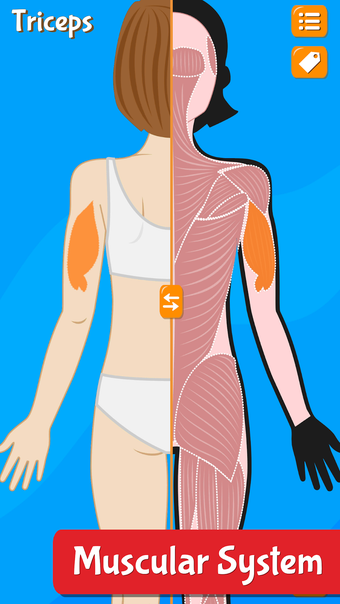

Anatomix es un juego de aprendizaje de anatomía humana que te enseñará a identificar todos los huesos del cuerpo humano y te permitirá explorar cada sistema en detalle. A medida que explores cada sistema, podrás identificar todos los huesos, músculos y otras estructuras.

Además de eso, podrás utilizar los diferentes huesos para identificar los diferentes sistemas.

La aplicación también te ayudará a identificar los diferentes huesos de tu propio cuerpo y te permitirá explorar cada sistema en detalle.